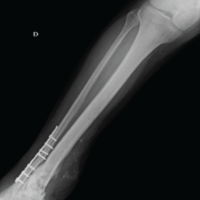

The patient’s post-operative course was uneventful. Sutures were removed at 2 weeks. At 4 months follow-up, the patient had significant improvement in ROM of the thumb with easy continuation of his occupational activities, normal grip, and no clinical or radiological signs of recurrence (Fig. 10).